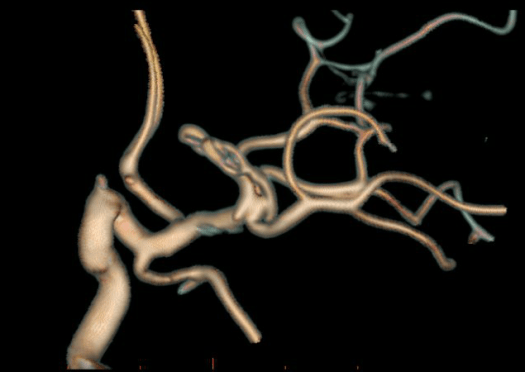

Clipping di aneurisma complesso M1-M2 di sinistra – ricostruzione biforcazione arteria cerebrale media

Angiografia cerebrale di controllo post-operatorio